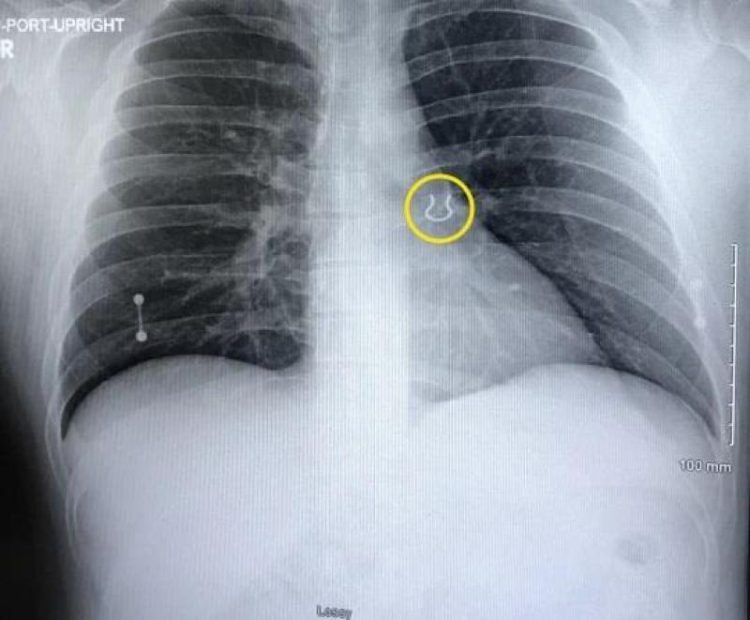

Man Who Lost Nose Piercing Five Years Ago Finds It Stuck in His Lung

A 35-year-old man was recently shocked to learn that the nose piercings he had lost one night five years ago had wound up in one of his lungs. A few weeks ago, Joey Lykins, a piercing enthusiast from Cincinnati, woke up in the middle of the night with a terrible cough. It felt like something […]